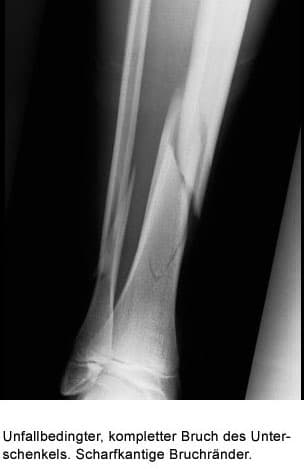

Beispiel: Ein 50-jähriger Mann war sportlich noch nie aktiv. Die Stabilität seines Schienbeines hat sich an die Bürotätigkeit angepasst. Plötzlich beginnt er zu joggen, täglich etwa 6 Kilometer. Ein Ruhetag pro Woche wird eingelegt. Für sein relativ schwaches Schienbein bewirkt das Joggen eine Verformung von etwa 0,4%. Beim Knochenumbau wird der mechanisch minderwertige Faserknorpel aufgebaut. Zeit zur Umwandlung in den festeren Lamellenknochen ist nicht vorhanden, weil der Mann täglich joggt. Nach etwa 3 Monaten tritt ein Ermüdungsbruch des Schienbeines auf, spürbar durch zunehmende Schmerzen bei Belastung, tastbar an einer druckschmerzaften Verdickung des Schienbeines. Das Röntgenbild zeigt den Frakturspalt. Eine Entlastung des Beines über etwa 4-6 Wochen führt zur Ausheilung. Überlastung in diesem Sinne bedeutet eine ungewohnte Belastung. Hierher gehört auch die Marschfraktur von Mittelfußknochen bei Rekruten, die zuvor lange Märsche nicht gewohnt waren.